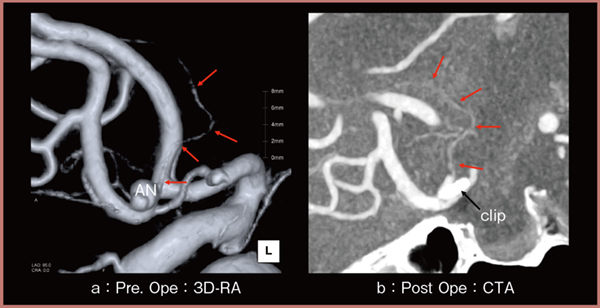

図3は,クモ膜下出血でクリッピング術が施行された患者(73歳,女性)の術前後の画像であるが,術前3D-DSA(a)で描出されたsubcallosal artery(←)が,術後にAquilion Precisionで撮影したCTA(b)でも描出されており,温存できていることが確認できる。

われわれは術前3D画像にsubcallosal arteryを融合させた画像を提供しており,脳神経外科から術前シミュレーション画像として高い評価を得ている。このように,高精細CTはsubcallosal arteryの描出能が高いと言える。

図3 Subcallosal arteryの描出

(参考文献3)より引用転載)